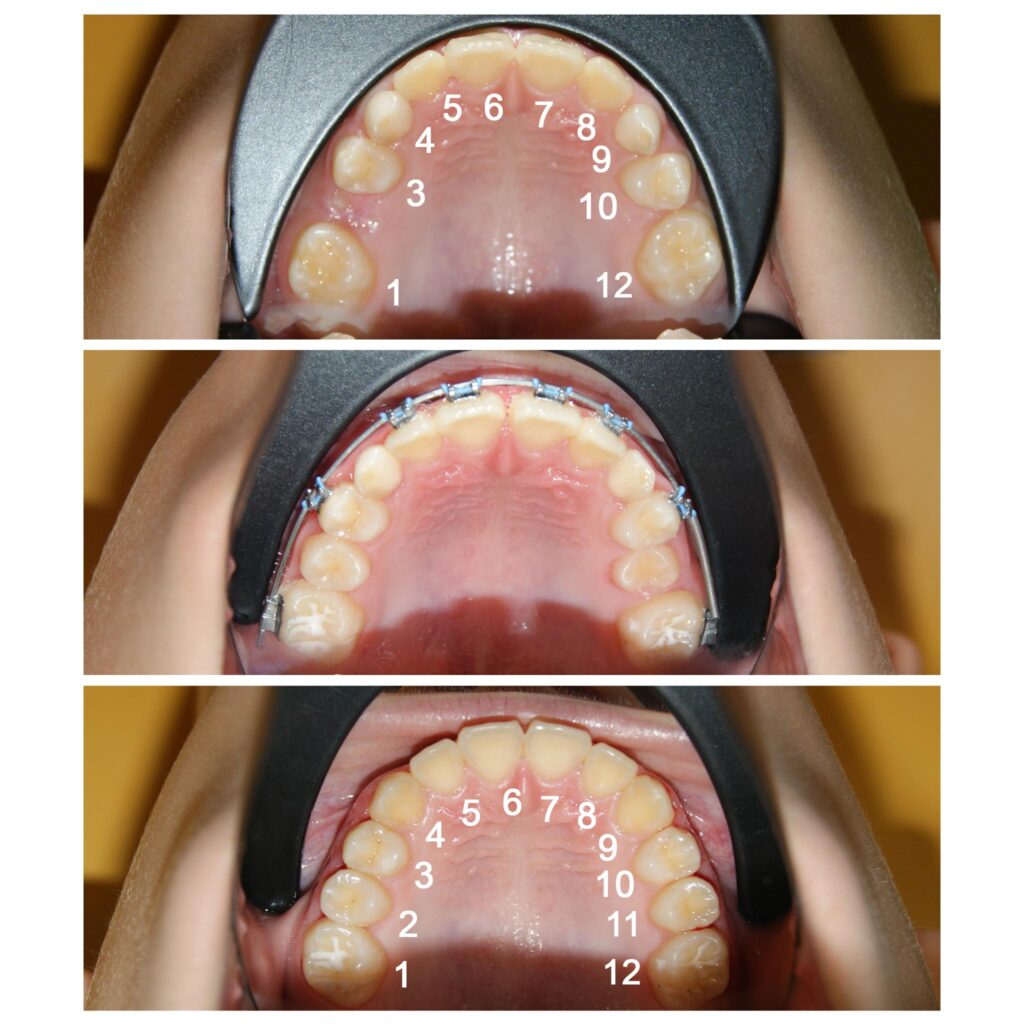

Recâștigarea spațiilor pierdute pentru dinții numerotați cu 2 si 11. Dacă nu am fi pus aparatul ortodontic fix dinții ar fi rămas blocați în intriorul osului, cu consecințe dramatice